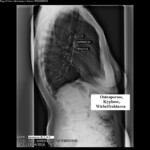

I. Οἱ ἁπλὲς ἀκτινογραφίες: Ἔχουν τὸ μειονέκτημα ὅτι θὰ δείξουν ὀστεοπόρωση ὅταν ἡ νόσος εὑρίσκεται σὲ προχωρημένο στάδιο. Δὲν πρέπει ὅμως ν’ ἀγνοεῖται καὶ ἡ δόση τῆς ἀκτινοβολίας, ἰδία ὅταν διενεργοῦνται στὴν σπονδυλικὴ στήλη (εἰκ 1η ΑΡ ἐπάνω).